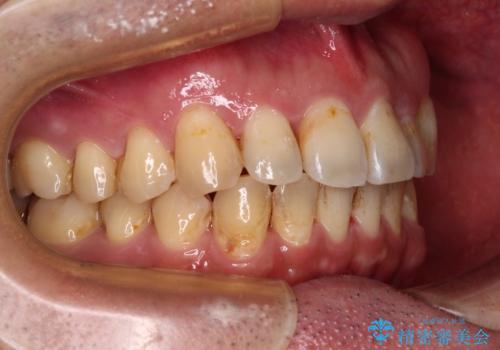

インビザライン矯正では苦手とする舌側転位した前歯をスムーズに改善することができました。

矯正治療により歯磨きがしやすくなったので、虫歯予防のセルフケアが行いやすい環境となりました。